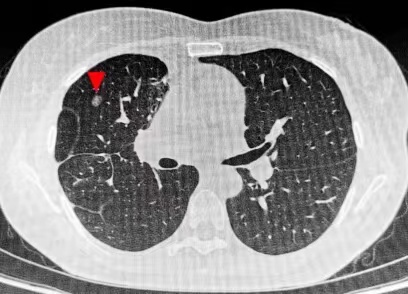

患者李女士今年47岁,2021年体检发现右肺多发结节,无咳嗽、咳痰、胸闷、胸痛等症状。后在当地医院及时进行胸腔镜下右肺上叶、中叶、下叶多处切除术,术后病理诊断均为腺癌。李女士术后一年发现右肺中叶新发磨玻璃结节,后定期随访发现结节呈增长趋势,考虑异时性多原发肺癌可能性大。

由于既往右肺手术切除范围大,且术后胸腔粘连,再次手术创伤大,患者多方辗转后被推荐前往华西医院就诊治疗。围绕患者病情,刘伦旭教授、蒲强教授、廖虎副教授团队经过讨论,总结为:第一,患者肺癌术后,双肺多发小结节,其中右肺中叶新发混合密度结节随访过程中逐渐增大,有干预指征。患者三年前已行手术切除右肺多处组织,为避免再次手术影响呼吸功能和生活质量,可考虑选择经皮穿刺的肺结节射频消融治疗。第二,该结节大小为0.8×0.6cm,体积较小,既往手术的吻合钉可能干扰穿刺路径,常规方法难度大、风险高,可选择可精准定位导航的机器人进行辅助穿刺。在与患者及家属充分沟通后,团队决定采用穿刺导航机器人辅助、联合CT完成肺结节射频消融术。